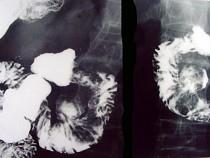

问题 男,55岁,中上腹隐痛多年,剑突下压痛,影像检查如图,最可能的诊断是 ( )

选项 A.十二肠溃疡 B.十二指肠憩室 C.十二指肠癌 D.十二指肠重复畸形 E.十二指肠穿孔

答案 B